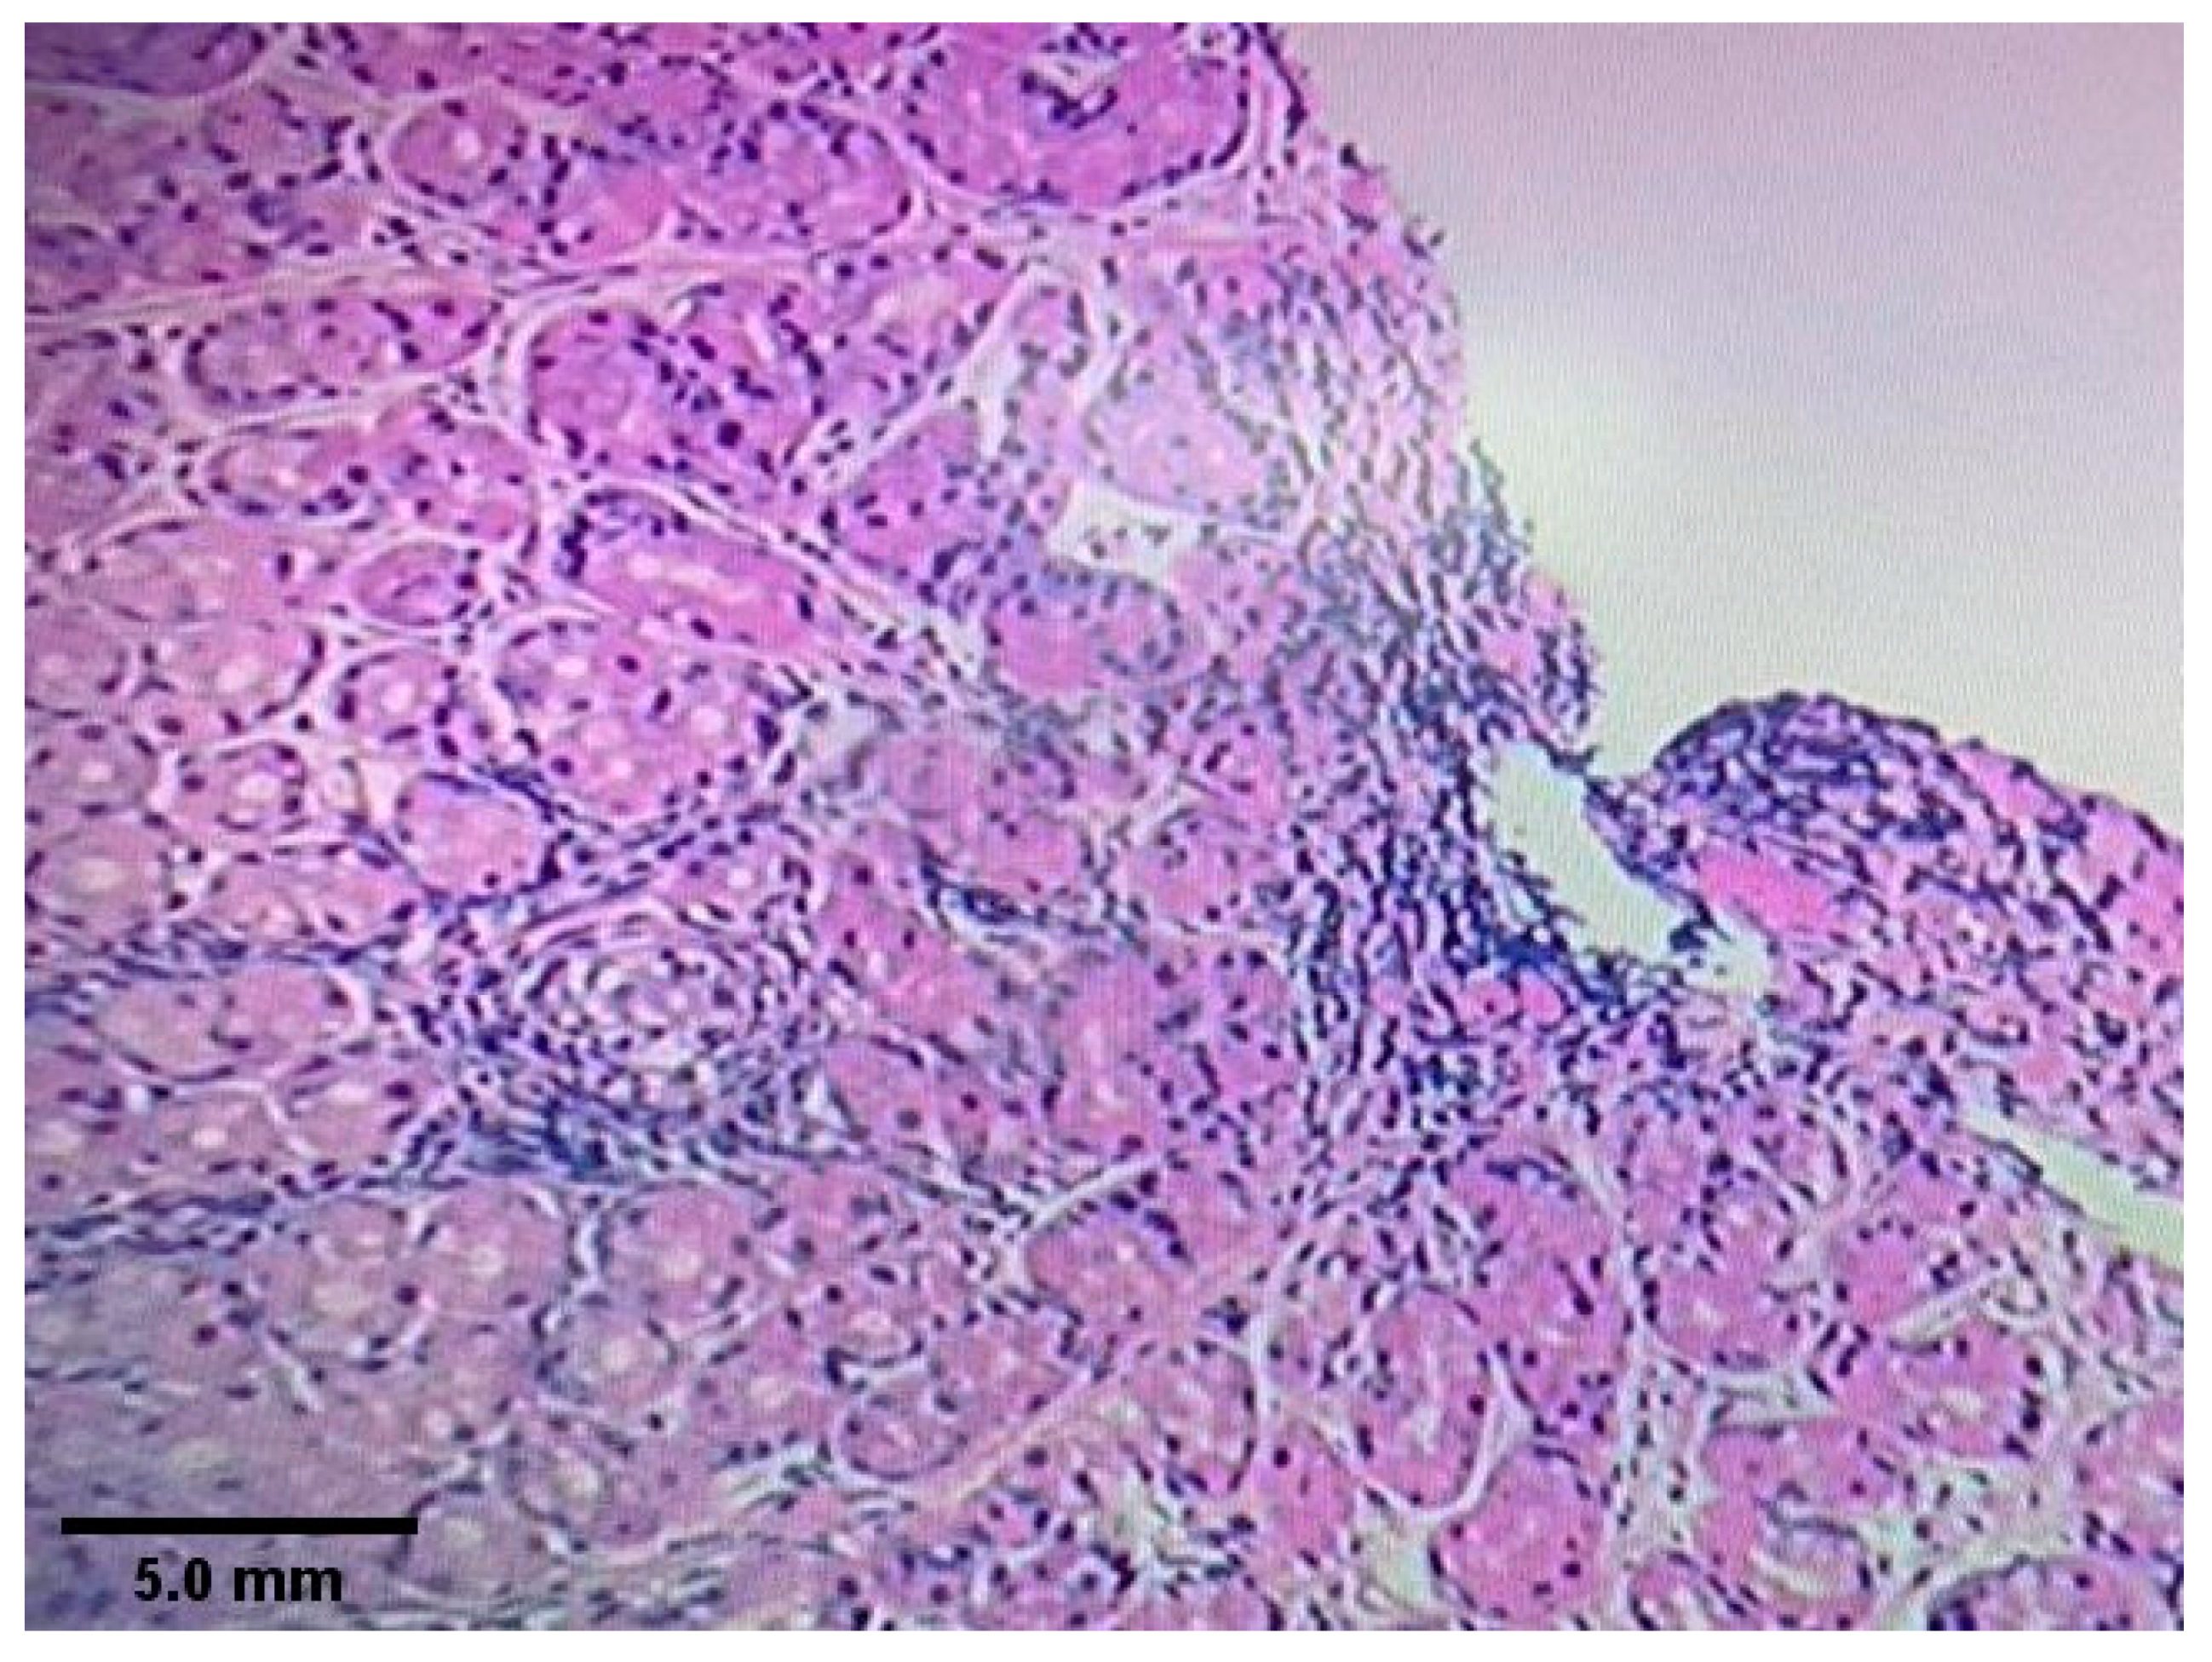

2.2. Endoscopy